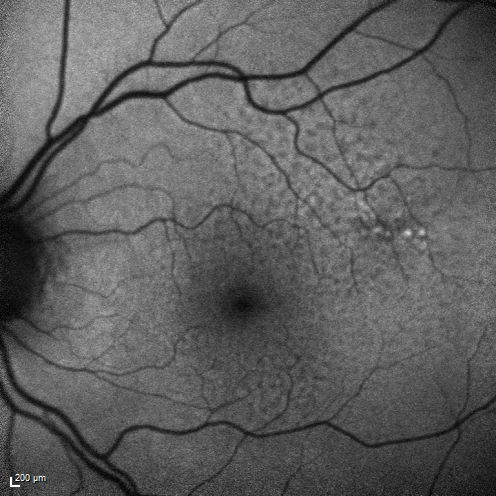

Reticular Macular Disease (Dry Macular Degeneration) - Fundus Autolfuorescence

85 year old woman with 20/25 vision OU and reticular macular disease